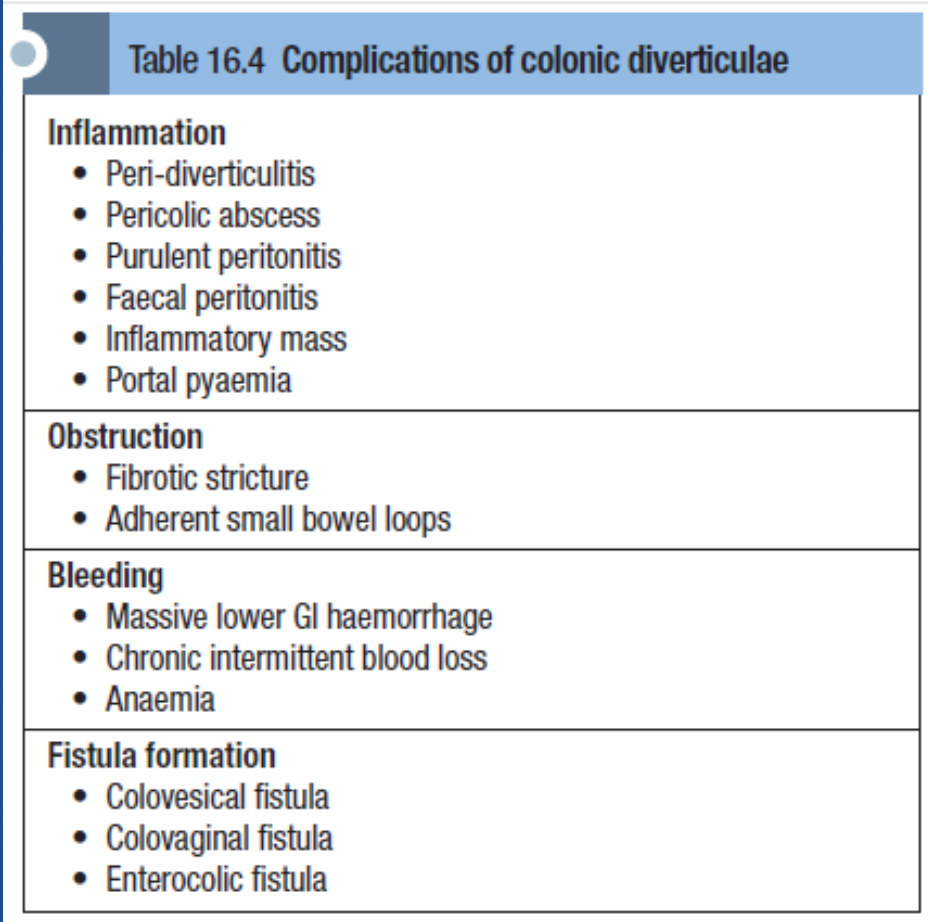

| Complication Category | Specific Complication |

|---|---|

| Inflammation | Peri-diverticulitis |

| Pericolic abscess | |

| Purulent peritonitis | |

| Faecal peritonitis | |

| Inflammatory mass | |

| Portal pyaemia | |

| Obstruction | Fibrotic stricture |

| Adherent small bowel loops | |

| Bleeding | Massive lower Gl haemorrhage |

| Chronic intermittent blood loss | |

| Anaemia | |

| Fistula formation | Colovesical fistula |

| Colovaginal fistula | |

| Enterocolic fistula |